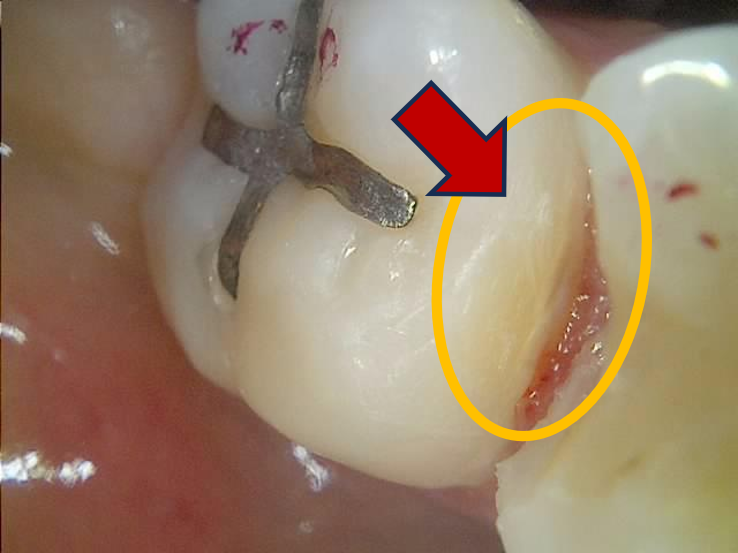

조금씩 모습을 드러내는 인접면 우식.

CT에서 상아질까지 진행이 확인된 충치라, 상당히 깊다.

CT로 확인된 인접면 충치 치료를 위해 충치 제거 시작

저건 CT 아니면 못 찾았을듯..

인접면 충치 제거 완료 후 깊은 우식 확인